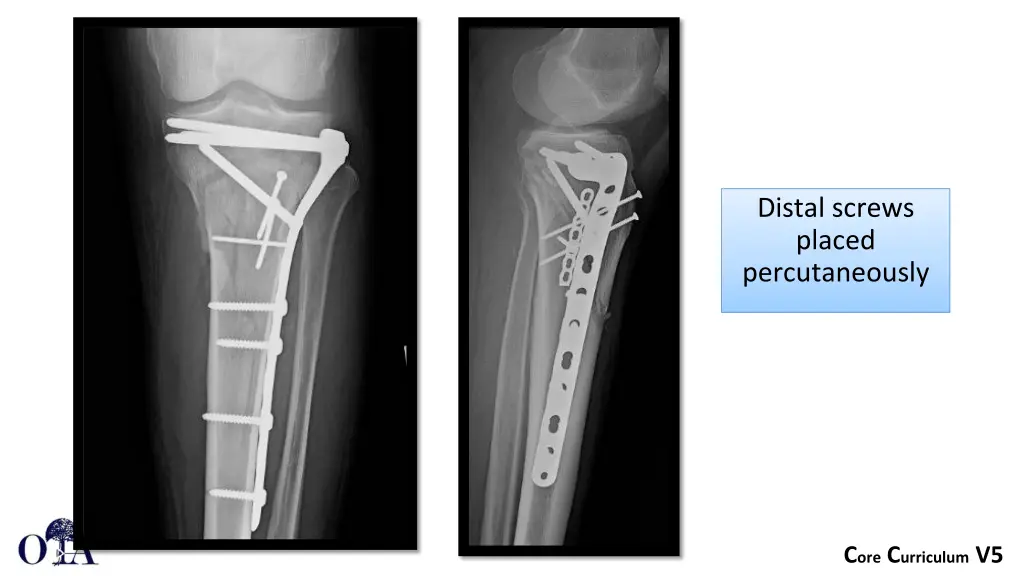

Proximal Tibia Plate can be slid in submuscular fashion along the anterolateral tibia with distal fixation placed percutaneously Core Curriculum V5

Limited incision with clamp and plate assisted reduction Core Curriculum V5

Distal screws placed percutaneously Core Curriculum V5